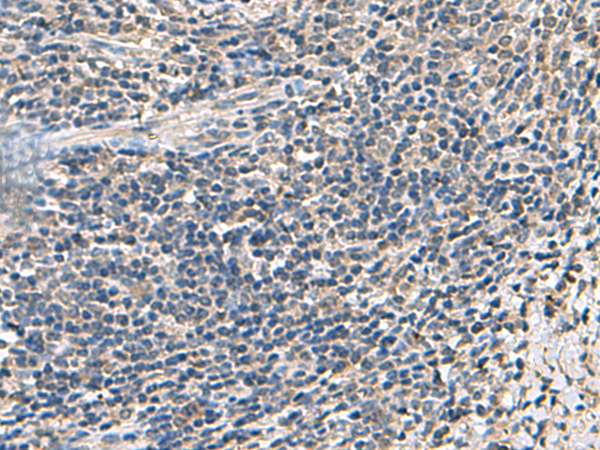

IHC positive control: |

Human cervical cancer |

IHC Recommend dilution: |

50-200 |